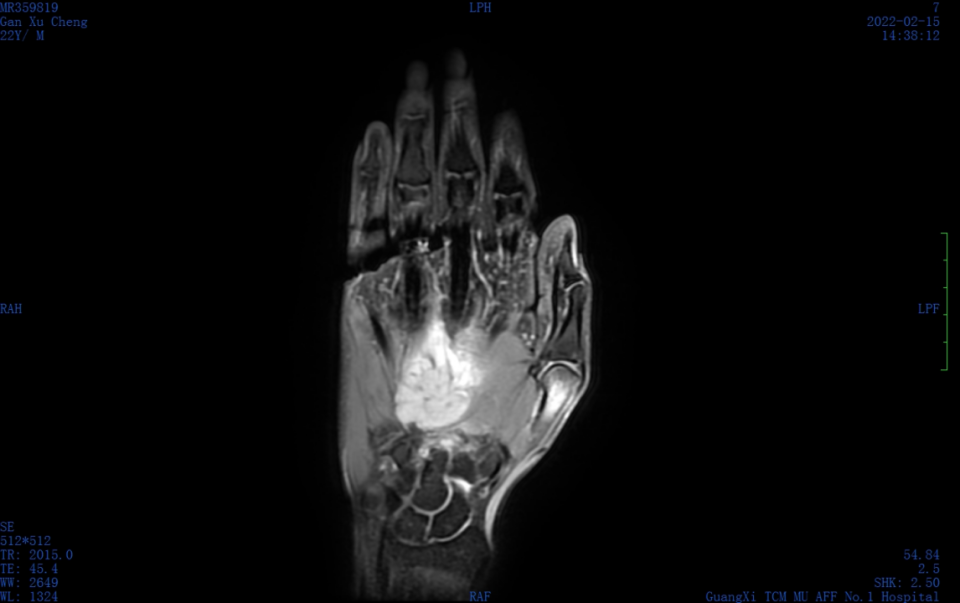

入院行超声检查,可见右手掌背皮下探及一实质性低回声区,范围约 8.1 cm × 3.5 cm × 3.1 cm,与周围组织分界不清,形态不规则,内回声不均,内可见强回声伴声影;

内另见第 3 掌骨骨质破坏、骨皮质连续性中断,内可见低回声区,范围约 3.0 cm × 1.8 cm,边界不清,内回声不均。

CDFI:低回声区内可见稍丰富点棒状血流信号。超声提示:右手掌背皮下不规则低回声区,第 3 掌骨骨质破坏,性质待定,考虑恶性可能,请结合其他检查。

图片图 1 右手背肿物二维超声声像图:不规则实质性低回声,内可见强回声,伴第 3 掌骨骨质破坏